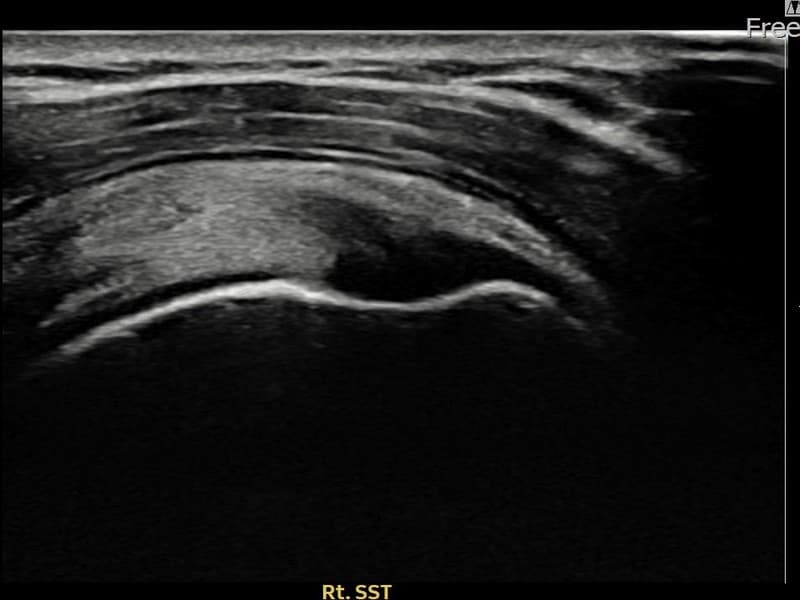

施術前

術前超音波にて右 棘上筋腱 付着部部分断裂・右肩棘上筋腱のエコー不連続と腱欠損(10mm × 4mm (腱厚の約42%欠損))を確認。術後超音波では断裂部位が再生組織で充填され、腱の連続性回復とエコーパターンの正常化が確認されました。